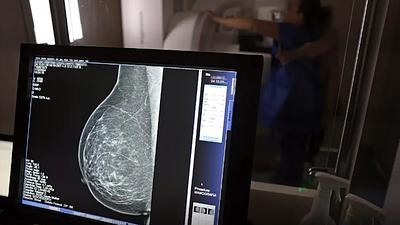

O Brasil tem uma cobertura muito baixa de mamografias: 24%. O ideal recomendado pela Organização Mundial da Saúde é de 70%.